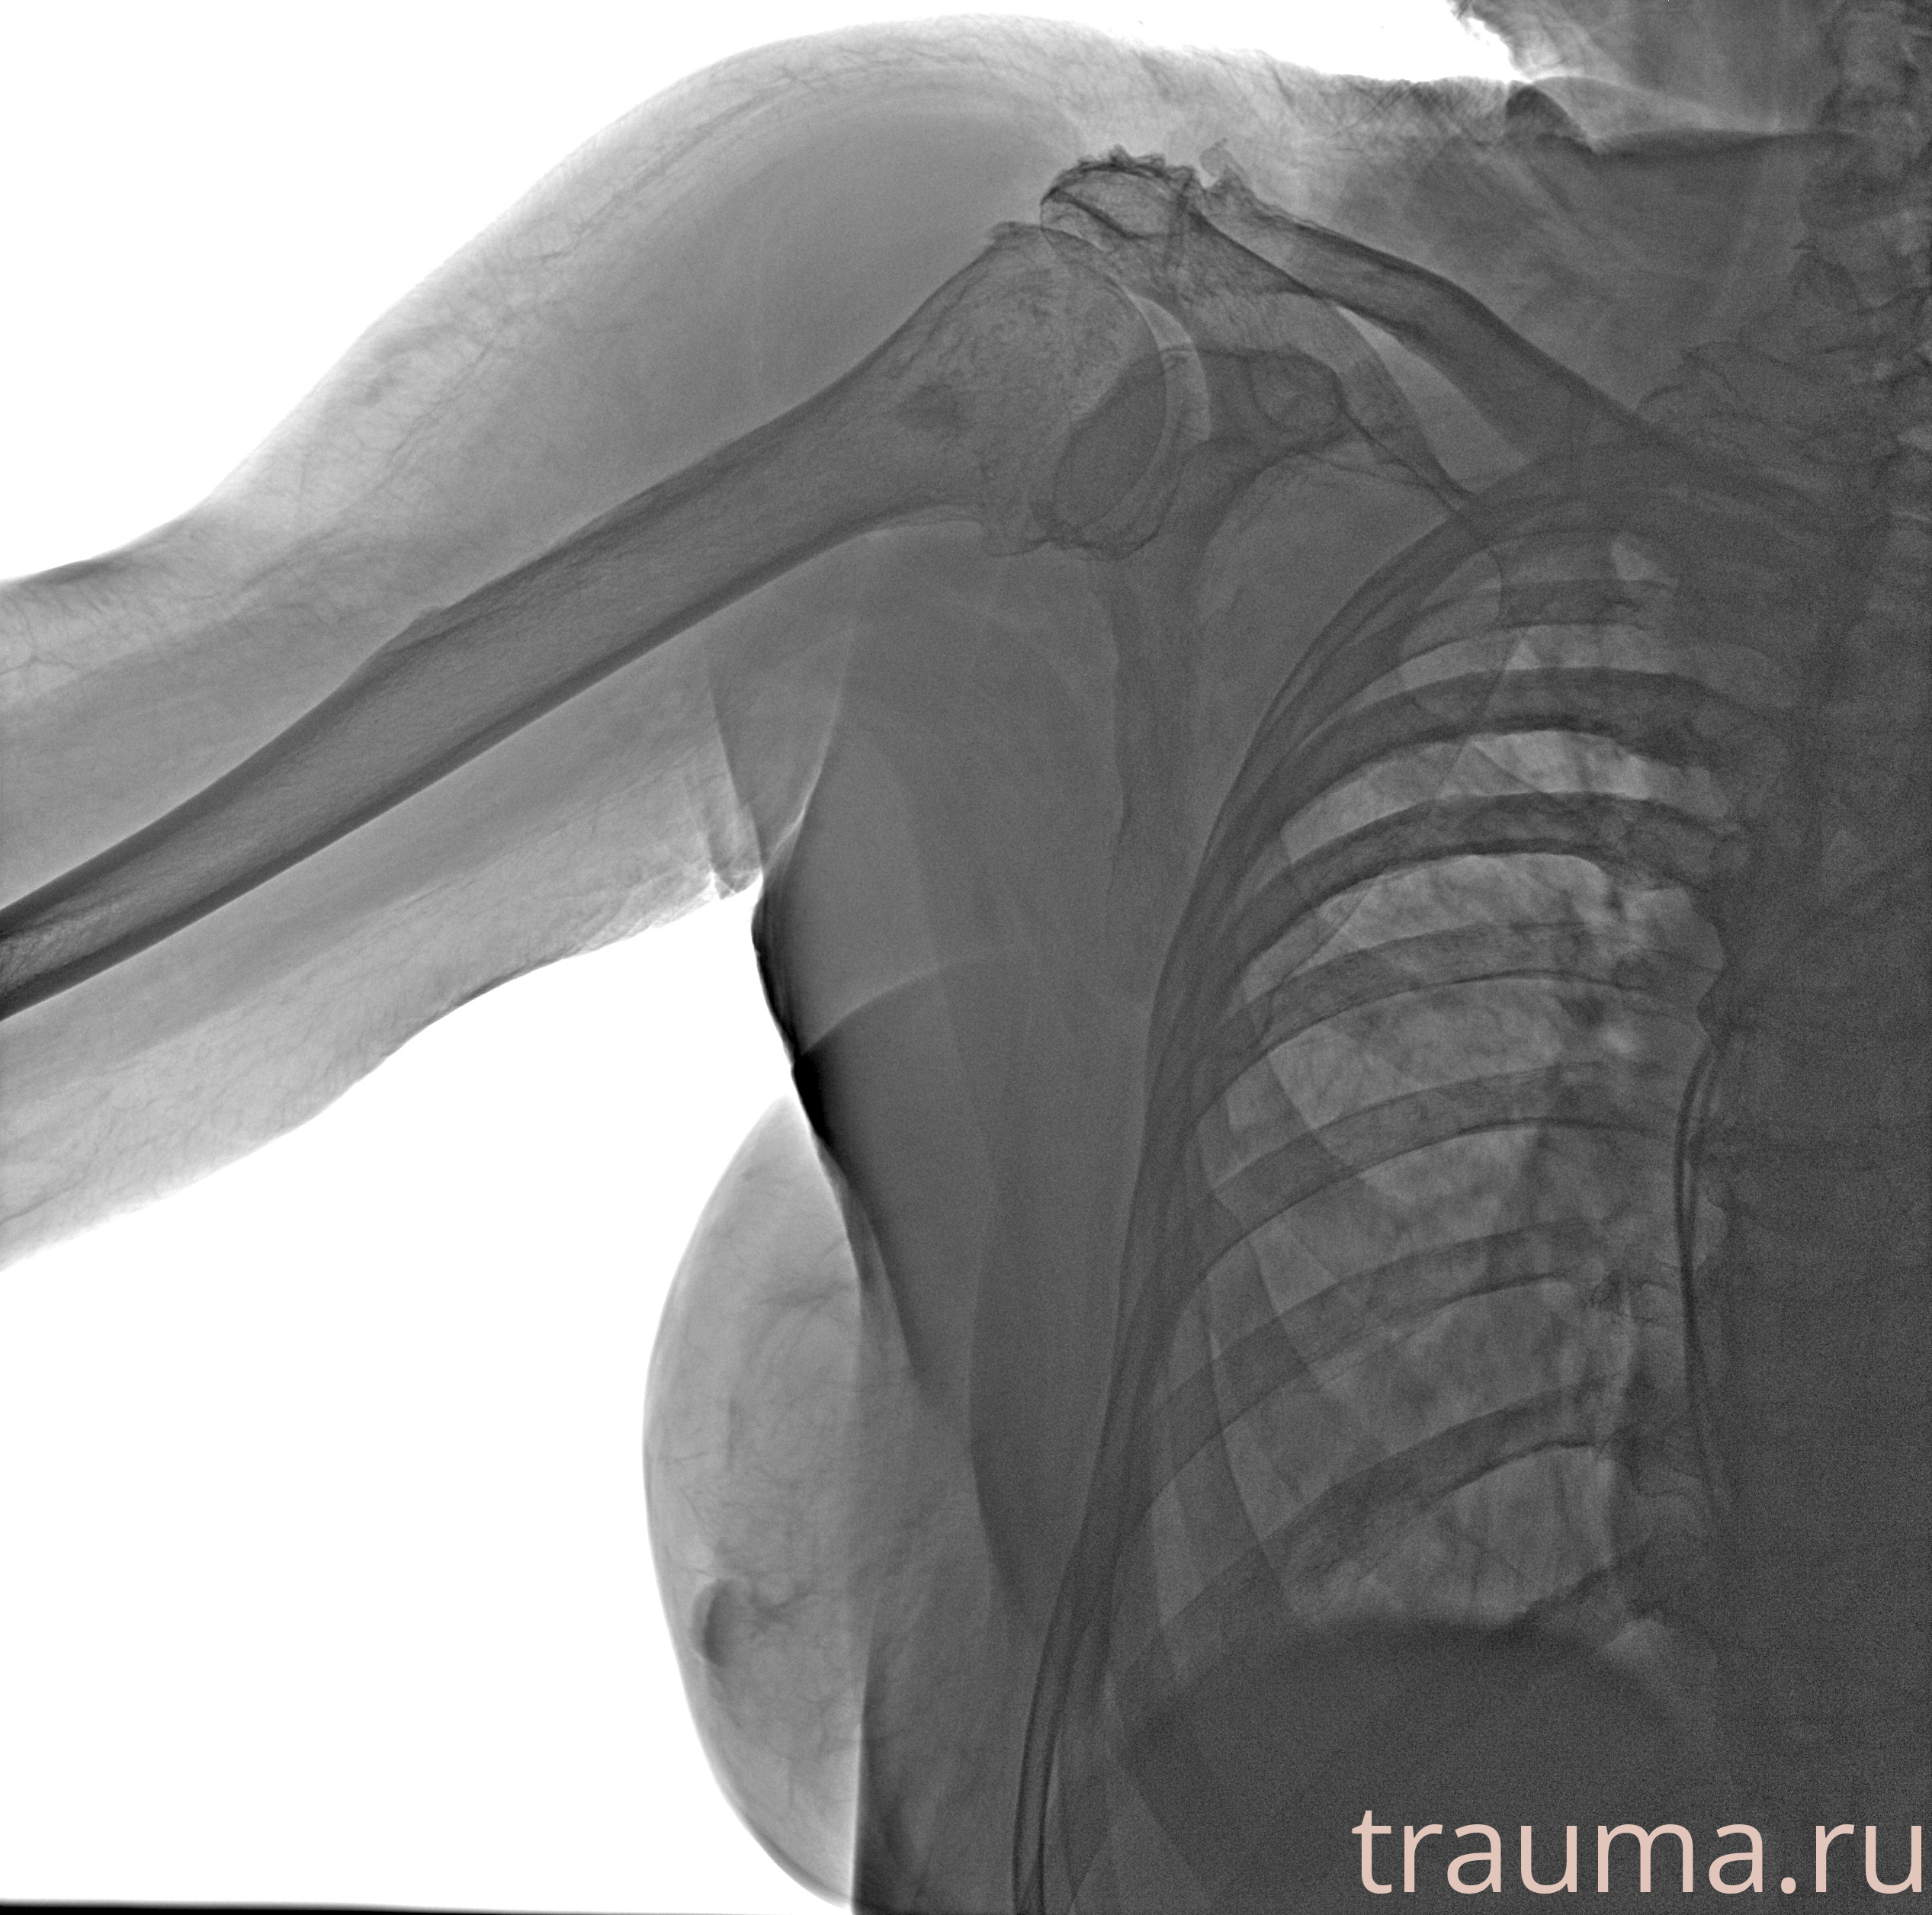

Рентгенограммы

Рентген на дому: по вашему адресу приезжает врач-рентгенолог, травматолог-ортопед с мобильным рентгеновским аппаратом, проводит диагностику травмы или заболевания, делает необходимые рентгенограммы, дает рекомендации по дальнейшему лечению. Получить качественные снимки в домашних условиях возможно благодаря уникальной методике, разработанной МосРентген Центром для института  Склифосовского